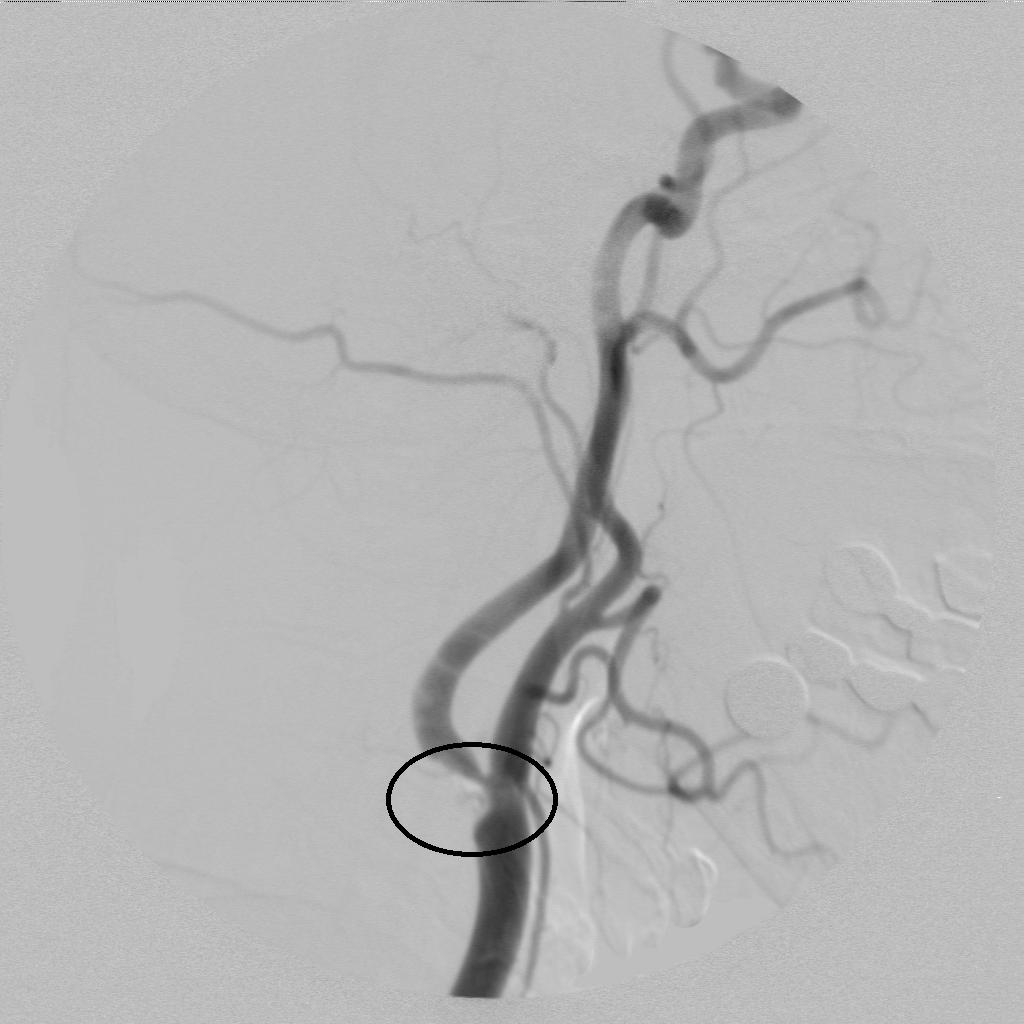

脑血管造影术发现右侧颈内动脉起始部狭窄!

术中进行血管再通治疗